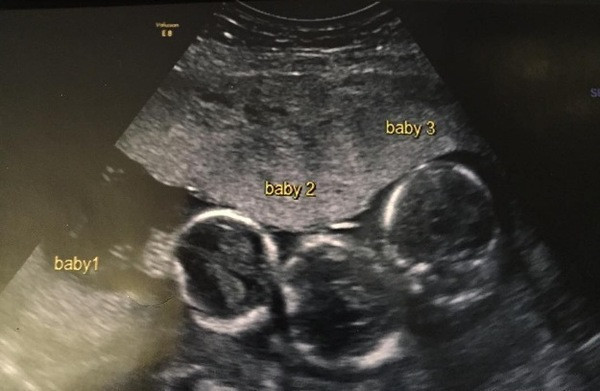

İNGİLTERE'nin Liverpool şehrinde yaşayan Indiana isimli bir kız çocuğu sahibi Becki-Jo Allen ve Liam Tierney çifti, milyonda bir gerçekleşen olayın konusu oldular. oktorlar 23 yaşındaki Becki-Jo Allen’a müjdeli haberi verdiğinde kadın şaşırdı kaldı. Beck-Jo doğum esnasında bir başka sürprizle daha karşılaştı. Meğerse çocuklar tek yumurta üçüzüymüş. Bunun gerçekleşme ihtimali 200 milyonda birmiş. Peki hikaye burada bitti mi sandınız? Hayır hikayenin geri kalanı büyük bir sürpriz.

Aile kızlarına kardeş istiyordu ancak üçüzleri olacağını tahmin edemediler. Hamileliğinin ilk haftalarında Becki-Jo hastalandı ve başı ağrımaya başladı. Ultrasona girince üçüzleri olacağını öğrendi. Becki-Jo, Liverpool Echo’ya “Hayatımın en büyük sürpriziydi! Sülalemizde üçüzleri olan kimse yok. Haliyle çok şaşırdık” dedi. Hamileliğinin 31. haftasında Becki-Jo sezaryenle Roman, Rocco ve Rohan’ı dünyaya getirdi. Bebeklerin her biri 1.5 kiloydu ve altı haftalarını yoğun bakımda geçirdiler.